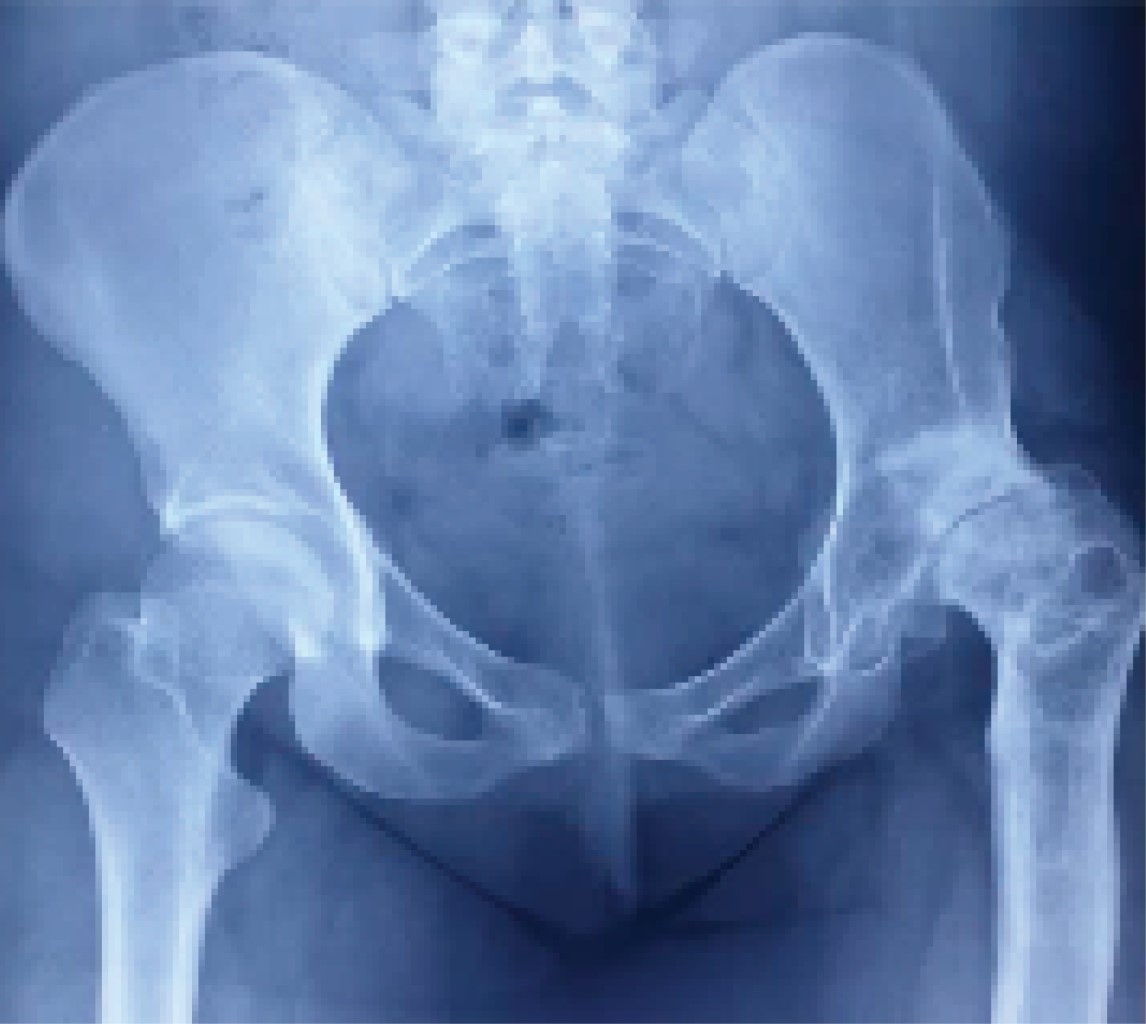

Mujer de 26 años con antecedentes de displasia del desarrollo de la cadera izquierda manejada quirúrgicamente durante la infancia con osteotomía de pelvis y osteotomía desrotadora de fémur, las cuales fueron fallidas (Figura 1), presentando secuelas en el desarrollo de su cadera durante su adolescencia con artrosis secundaria (Figura 2), con intenso dolor y limitación a la movilidad, impidiendo sus actividades cotidianas, motivo por el que se le realiza artroplastia total de cadera en clínica privada en el año 2017 a sus 22 años (Figura 3).

Figura 2